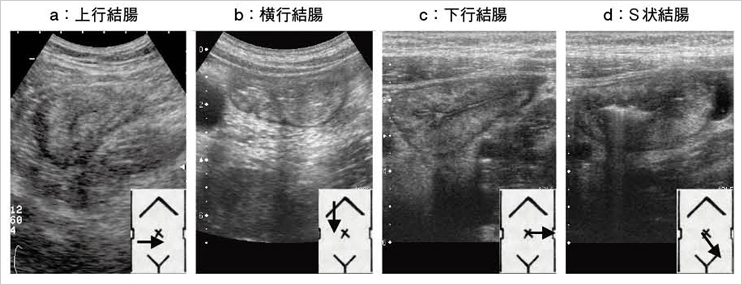

小児消化管超音波診断アトラス 消化管アトラス コンパクト超音波αシリーズ (電子版 メディの詳細情報

小児消化管超音波診断アトラス

診断と治療社

玉井浩

2005/04/01

4787811975

9784787811974

小児消化管超音波診断アトラス

診断と治療社

玉井浩

2005/04/01

4787811975

9784787811974